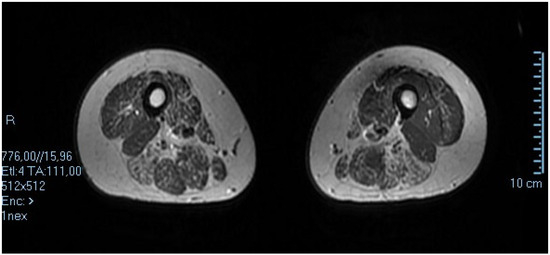

3. Case 2: An Asymmetric Limb-Girdle Myopathy Associated with the LDB3 Variant, Is Found in the Propositus (Figure 2)

| Present case | 3 years | Gait difficulties | Atrial dilatation, EF 50% | No | Distal | Axonal neuropathy | No |